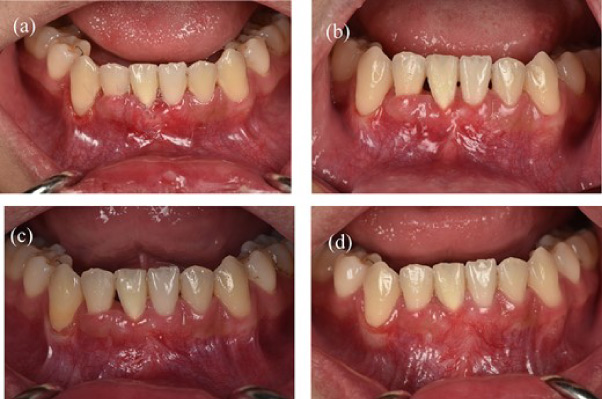

Before surgery: scaled the lower incisors and endodontic treatment. After 2 weeks, the inflammation of the gingival had decreased and we can start the gingival graft treatment and the surgical procedure is depicted below (Fig. 3). Local anesthesia then followed by meticulous preparation of the tooth surface using a high-speed handpiece. To prepare the root surface, a 24% ethylenediaminetetraacetic acid (EDTA) gel was used. To obtain an epithelialized connective tissue graft (CTG), tissue was harvested from the hard palate in the area from first premolar to first molar. The graft was carefully shaped and sized based on the specific measurements of the gingival recession defect. A specialized 15C blade was utilized for this precise procedure. Subsequently, a thin layer of epithelial tissue, ~0.5–1 mm in thickness, was eliminated from the graft using a high-speed handpiece and 2 mm round diamond bur, except for the specified epithelial section as illustrated in (Fig. 2a). A piece of connective tissue in size 13 × 13 × 1.5 mm was harvested to adequately cover the entire tooth root (Fig. 2b and c). Afterward, Emdogain was applied to the complete root surface, starting from the most apical bone level to maximize the therapeutic potential of Emdogain in facilitating tissue regeneration and promoting periodontal healing. On the right side, where gingival recession was observed on the teeth, a flap with varying thickness was raised. This flap featured a split-thickness technique in the papillae and vestibular sulcus, while maintaining full thickness at the center. An incision was created to alleviate tension, specifically at a location distant to the right canine. Through the sulcular access on the left side of tooth 41, the graft was inserted into the tunnel, and the epithelial segment of the graft was positioned over the exposed root. Subsequently, the graft sites on both the left and right central incisors were secured using 6–0 monofilament sutures. Finally, the gingival flap was repositioned to cover the entire connective tissue area (Fig. 4). Subsequent assessments and recording of the healing process were performed at intervals of 3 weeks, 2 months, 6 months, and 1 year through reevaluation and imaging (Figs 5 and 6).

Figure 5: Clinical images of postoperative follow-up. (a) 3 weeks. (b) 2 months. (c) 6 months. (d) 12 months.